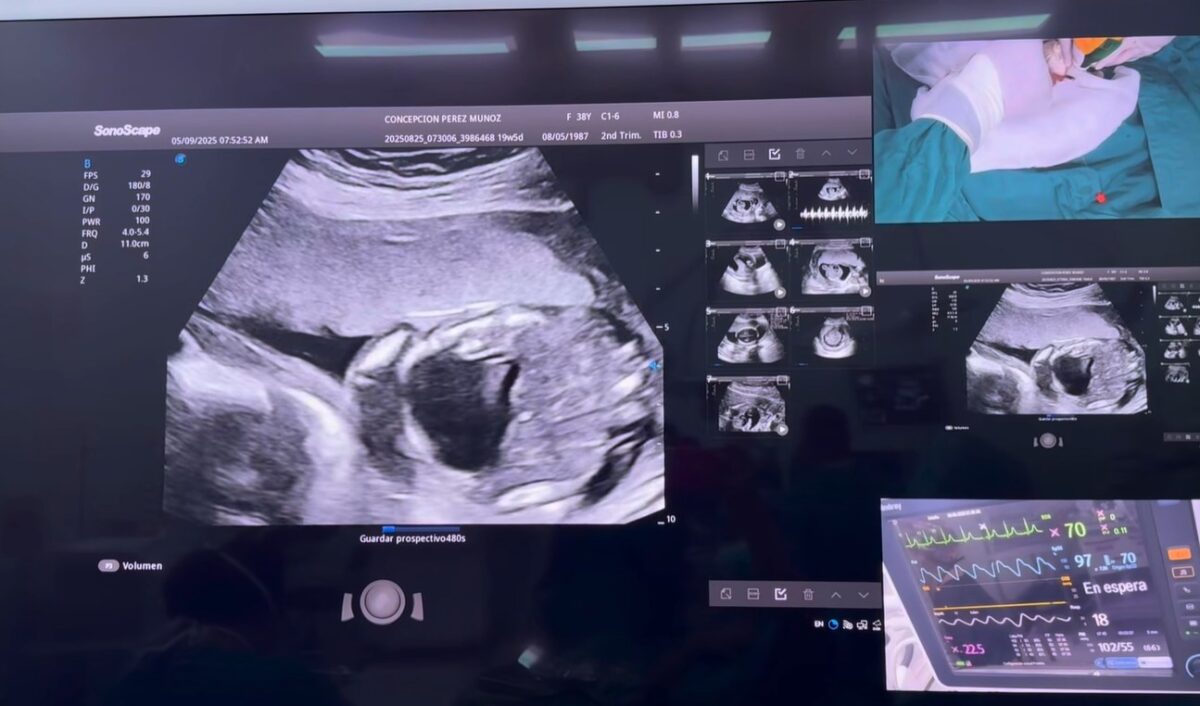

Un nuevo paciente recibió una oportunidad de vida gracias a la cirugía fetal intrauterina realizada en el Hospital Bertha Calderón.

El procedimiento, encabezado por el doctor Néstor Pavón, correspondió a la intervención número 284 y fue practicado a un bebé con hidrotórax fetal, extrayendo el líquido acumulado en los pulmones para favorecer su adecuado desarrollo.

Días antes, se llevaron a cabo las cirugías 281, 282 y 283 a madres originarias de San Ramón, Catarina, Masaya y Sébaco, quienes enfrentaban complicaciones por embarazo gemelar, hidrotórax fetal y tumor fetal.

La detección temprana realizada por especialistas en Medicina Materno-Fetal, junto con la atención gratuita de la Red de Cirugía Fetal, ha permitido que estas madres y sus bebés accedan a un tratamiento especializado y seguro.